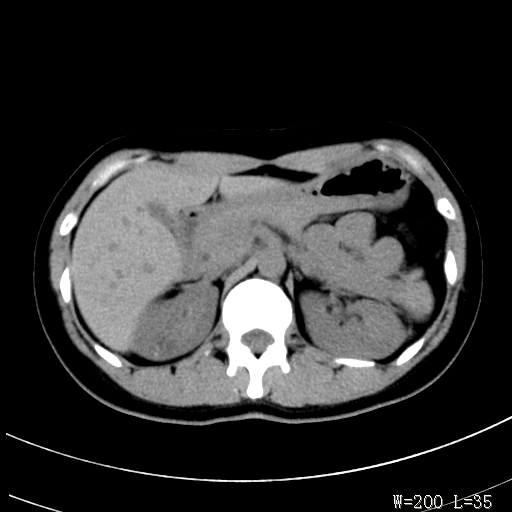

标题: CT25345:右肾占位。 [打印本页]

标题: CT25345:右肾占位。

女,30岁,右腰部胀痛3个月。

增强无明显强化,先考虑血管平滑肌脂肪瘤,建议作薄层扫描右mri检查,

感觉像囊肿.

囊肿!

考虑右肾近上极囊肿;建议必时行mri检查。